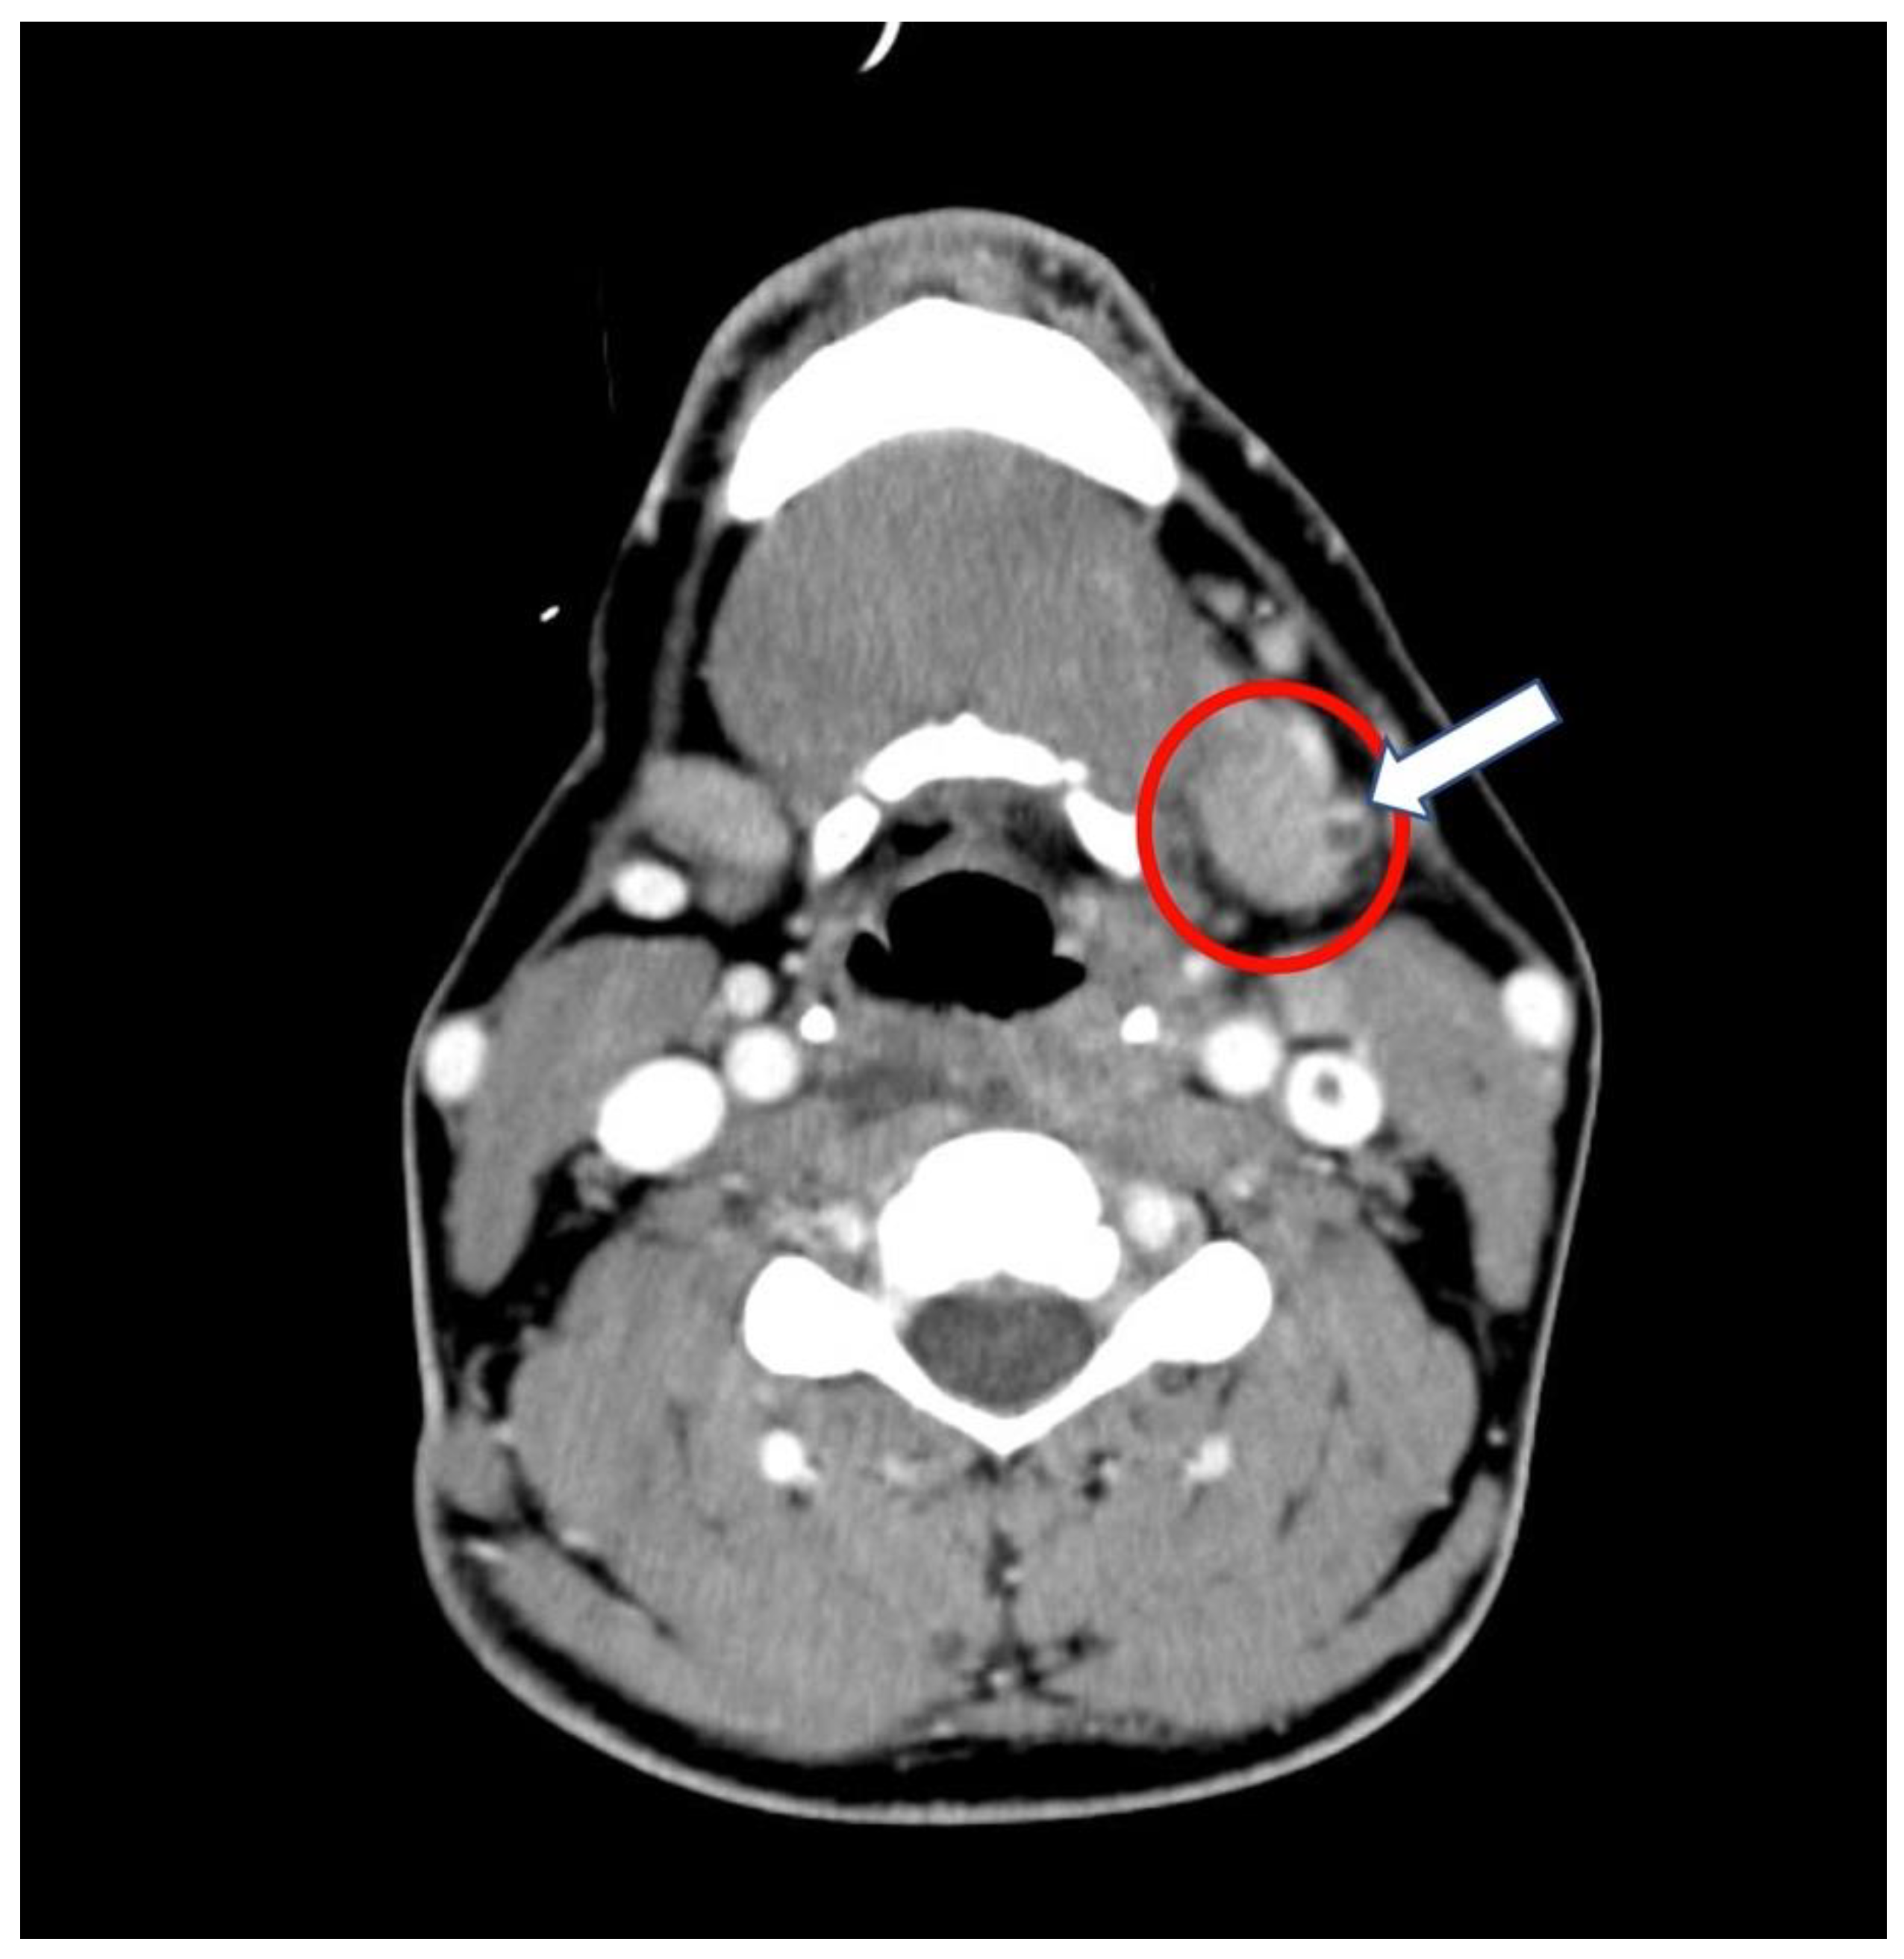

2. Case Presentation

2.1. History and Hospital Admission